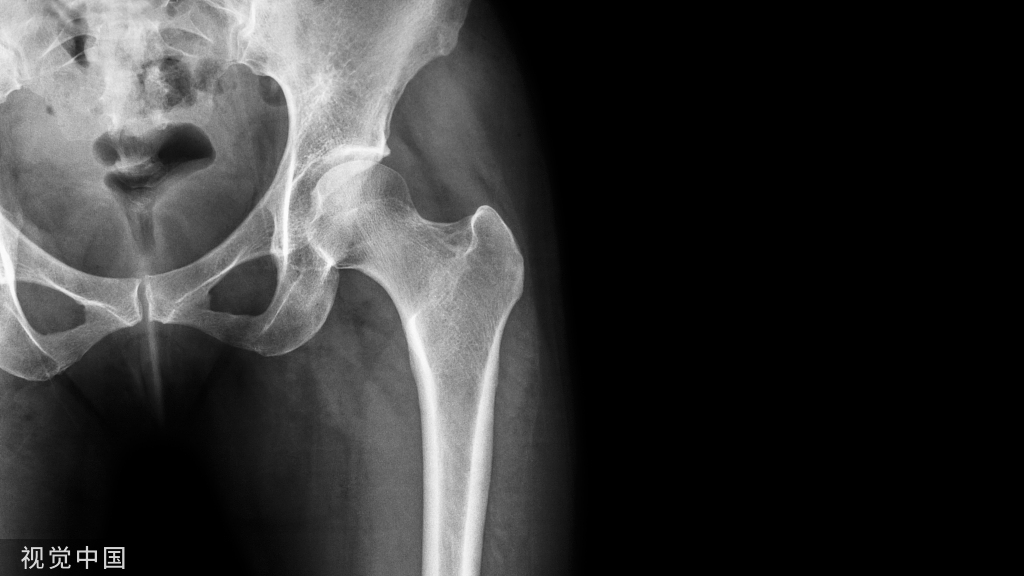

近年来,糖尿病的骨折风险越来越受到重视,糖尿病患者严重骨折与全因死亡率有关。T1DM和T2DM发生脆性骨折的风险都会增加,《糖尿病患者骨折风险管理中国专家共识》[1]指出虽然双能X线骨密度仪测得的骨密度能够在一定程度上反映非糖尿病患者的骨折风险,但却会严重低估了糖尿病患者的骨折风险。因糖尿病患者可以在相对于非糖尿病患者较高的骨密度下发生骨折,而且各种降糖治疗也可能对骨代谢产生影响,如何通过生化标记物早期判断糖尿病患者的骨折风险,并由此采取有效措施遏制糖尿病骨折的发生发展显得尤为重要。